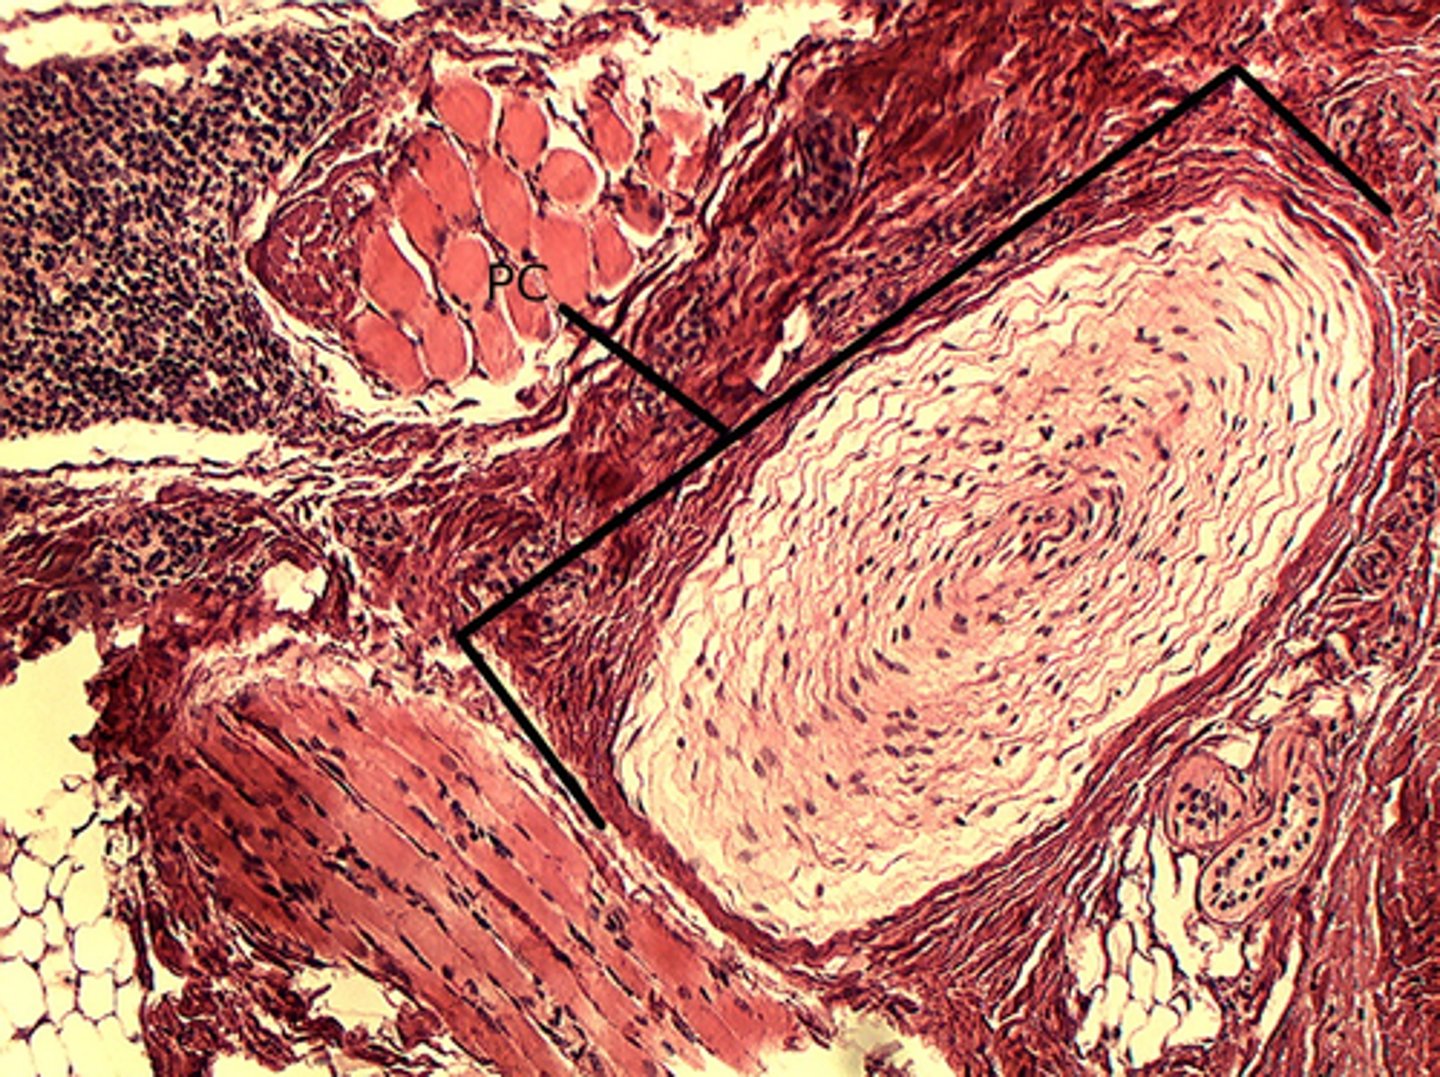

Lamellated corpuscles (Pacinian corpuscles)

what is this called?

Lamellated (Pacinian) corpuscles

what is the structure in the bracket called?

What is the red arrow pointing to?